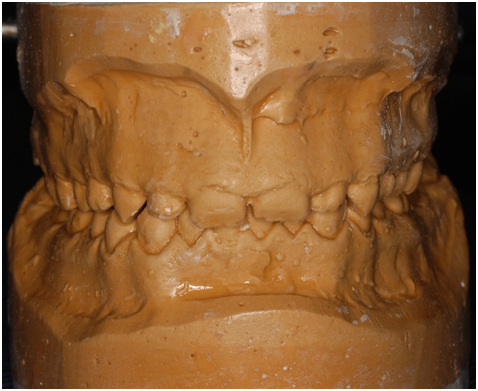

A 22 Yemeni male patient presented to the College of Dentistry clinics at the University of Dammam seeking cosmetic treatment with a chief complaint “I want to improve the way my teeth look " He reported no significant medical history. Patient has never been into the dental clinic. He stated his deciduas teeth were normal and his whole village complains of darkened teeth (brownish). A panoramic x-ray (Figure 1), intraoral pictures (Figures 2−6) as well as study casts were taken to diagnose the case (Figure 7). Upon examination, the patient was found to suffer from severely generalized discoloration of permanent teeth and moderate dental attrition resulting in shortening of the vertical dimension of occlusion (VDO). A class I occlusion with class I canine relation was present, with an over-bite of 4mm and an overjet of 4mm. The upper lip seems stretched with dropping mouth angles. The patient suffers from generalized marginal chronic gingivitis with no mobility or furcation involvement noticed. The treatment plan started with plaque control measures were conducted as well as patient education. The patient's esthetic problem caused by Fluorosis both teeth staining and facial appearance and occlusion. The treatment options available range from bleaching, porcelain veneers, full coverage ceramic crowns or porcelain fused to metal crowns. Due to the Fluorosis severity, the bond strength of the adhesive agent was questionable that eliminated the veneers option. Bleaching when tried had minimal effects. Finally, porcelain-fused to metal (PFM) crowns were selected to restore esthetics of anterior teeth, while posterior gold crowns were chosen to raise the occlusion posterior by 2mm. Treatment options were discussed with the patient who consents to the treatment plan.

Figure 1 Pre op OPG.